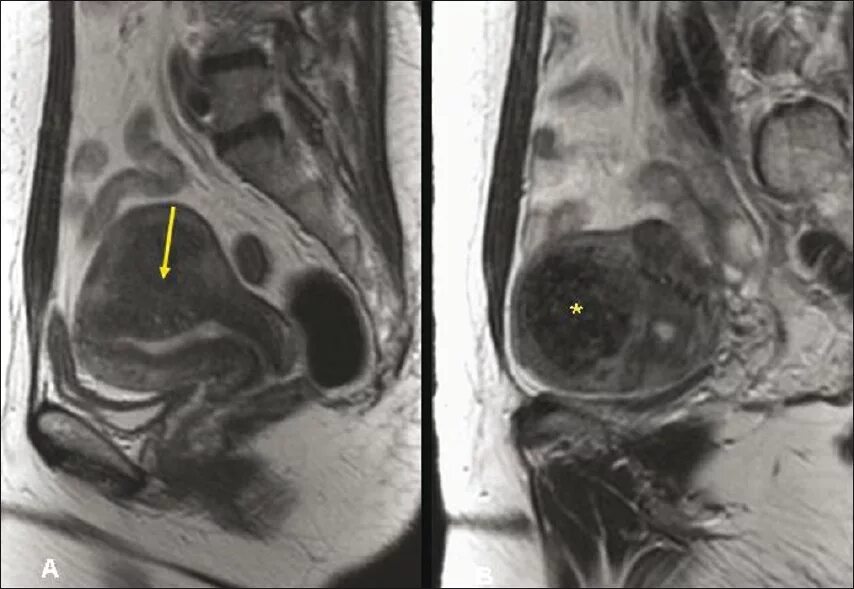

Аденомиоз диффузные изменения